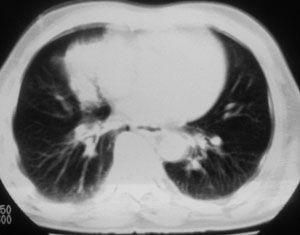

性别 男  62岁 因咳嗽及左肱骨剧烈痛疼数天来院检查。

右中央型肺癌并肱骨转移。

考虑右肺中叶肺癌并左肱骨转移伴病理性骨折。

支持右肺中心型肺癌并肺内及左肱骨转移伴病理性骨折

右肺中心型肺癌并中叶不张,左肱骨溶骨性转移并病理骨折。